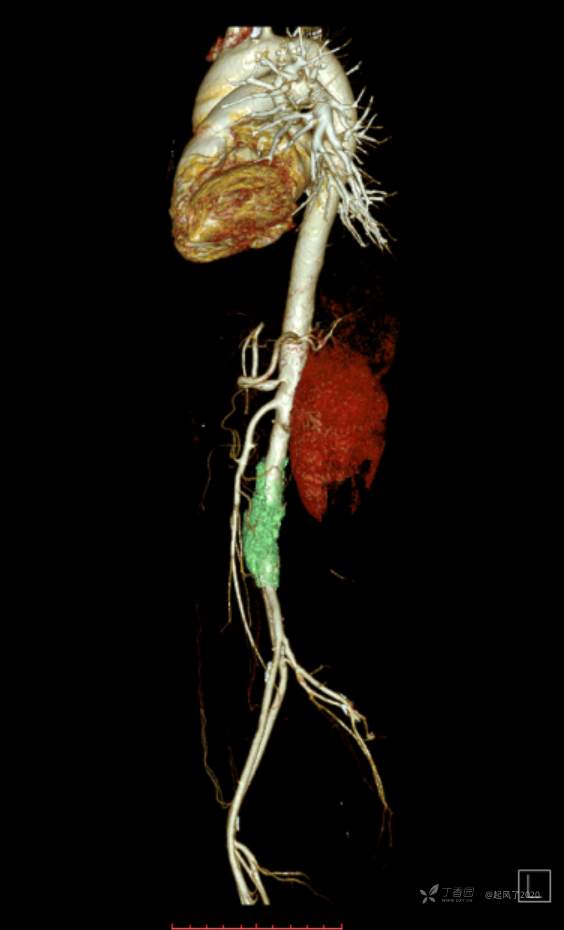

求助 | 女,61岁,下腹部、腰及双髋关节隐痛1月余

II型糖尿病10年余,既往饮食控制血糖在7~8左右,今年1月份开始服用二甲双胍;2009年4月因“子宫肌瘤、双侧输卵管慢性炎症”行子宫及附件切除术;2021年1月体检发现双侧甲状腺多发结节,较大者12*7mm;高血脂10余年,近1月开始规律服药,控制不理想;无高血压